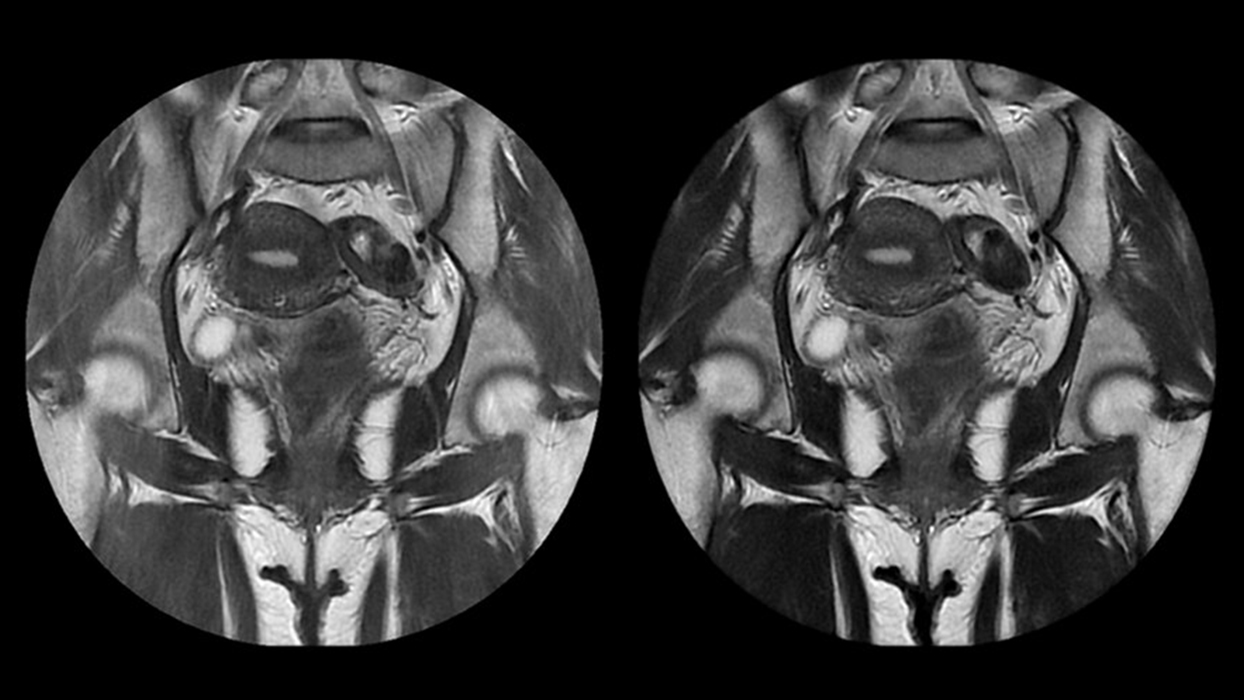

개에서 가장 많이 발생하는 심장질환이 판막폐쇄부전증이라면,

고양이에게 가장 많이

발생하는 질환은 '심근비대증' 입니다. 심근비대증은 심장 근육이

두꺼워지면서

심실내강이 좁아지고 몸 전체에 보내는 혈액이 감소하여 순환

장애가 발생되는 질환입니다.

주로 선천성인

경우가 많지만 고혈압, 갑상성기능항진증, 스테로이드 등 다양한

원인에

의해 심근이 두꺼워질 수 있으므로 주기적으로 검진을 통해서

검사 하는 것이 반드시 필요합니다.

심근비대증은 완치가 어려워서 정기적인 검진과 약물 치료를

꾸준히 병행해야하는

질환입니다. 샤인동물메디컬센터는 일반적으로 취급하기 어려운

최신식 약물들을

적극 도입하여 치료에 적용하고 있습니다. 뿐만 아니라 많은 임상

경험을 통한

심근비대증 치료에 최적화된 심장혈관센터를 운영하고 있습니다.